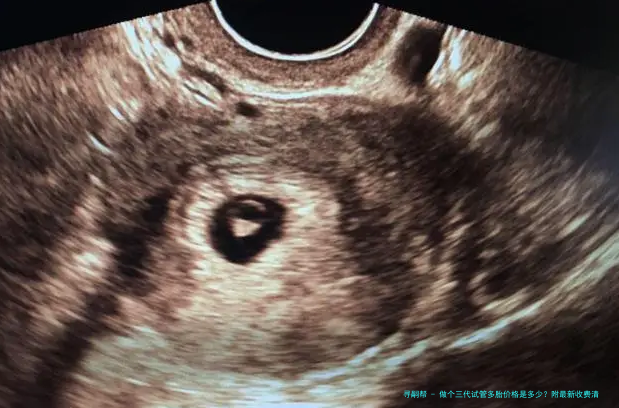

试管婴儿通过体外受精和胚胎移植的方式帮助不行自行受孕的夫妻完成生育心愿。这个技术慢慢形成为解决试管婴儿问题的有效手段。

三代试管婴儿是近年来发展起来的一项新技术,对比2代试管婴儿具有更高的成功率。它选用了新一代辅助生殖器械和先进的胚胎筛查技术,可以提高受孕率并减轻遗传病症风险。